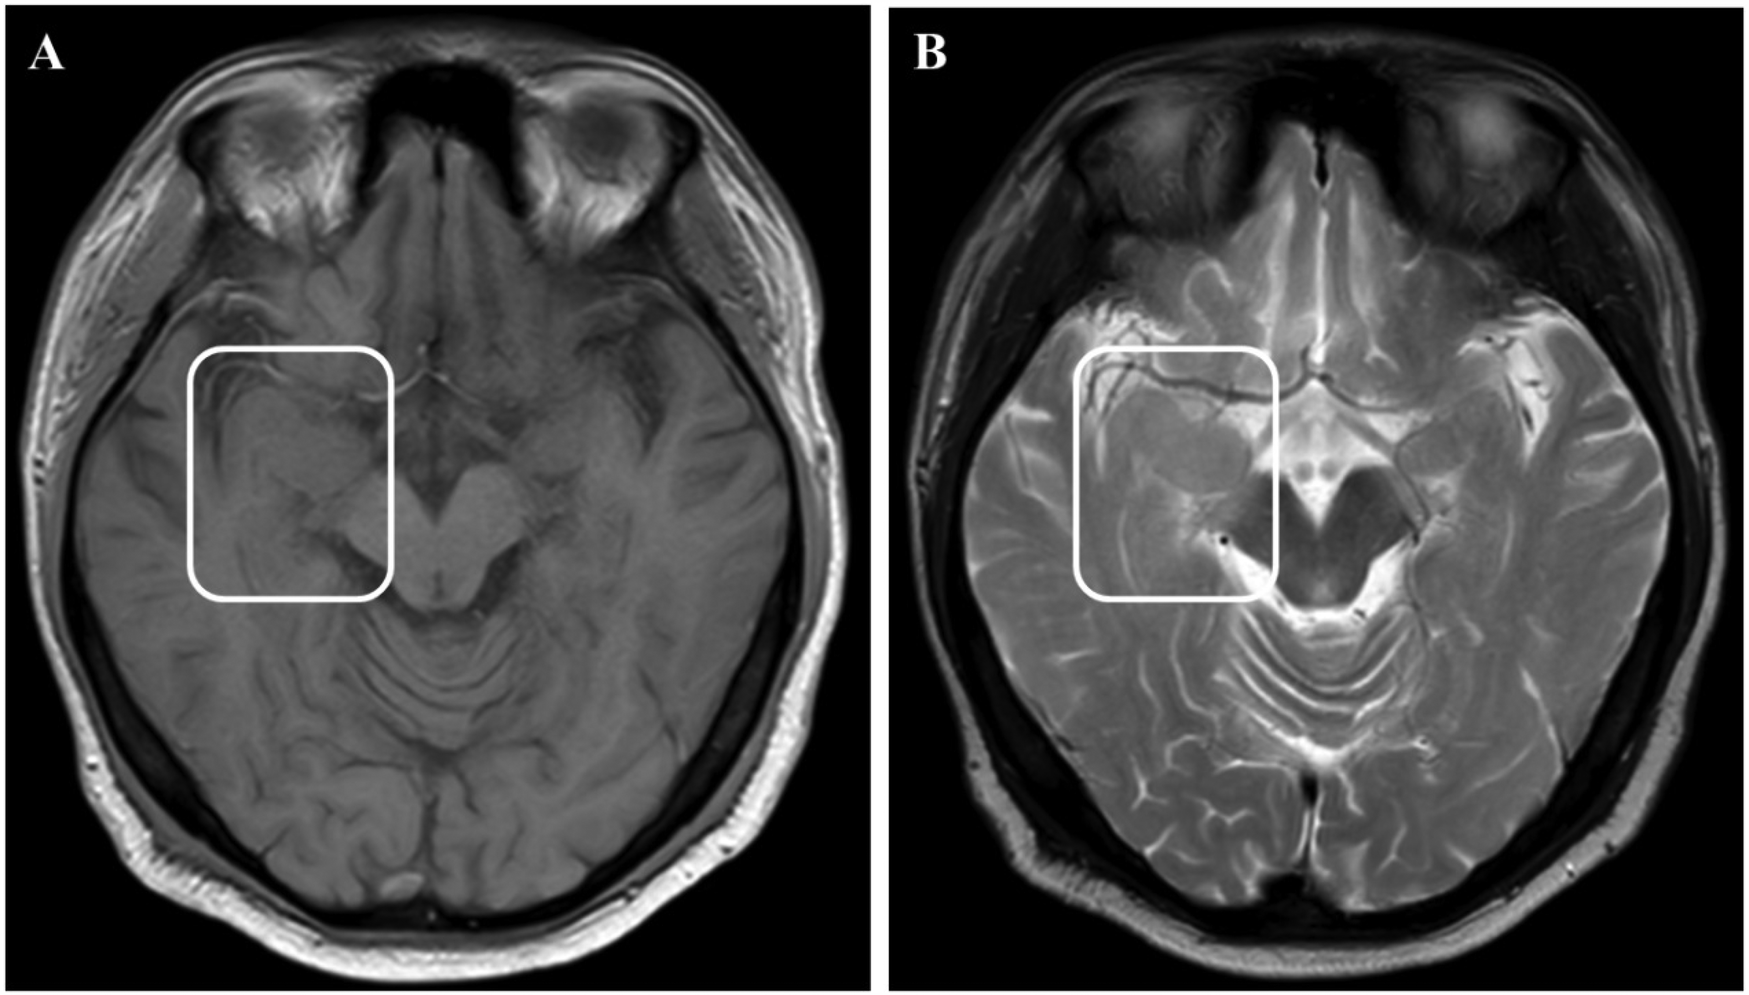

Figure 2

MRI images showed enlargement of the right amygdala and hippocampi. (A) showed T1 weight image. (B) showed T2 weight image.

Physical examination during his hospitalization revealed no abnormal findings in his cognitive function. CSF tests showed normal cell count, protein, glucose, and chloride levels. Long-term electroencephalogram (EEG) examination revealed epileptiform electrical discharges in the right frontal and anterior temporal areas, and slowing waves in the right frontal and the temporal areas (Figure 1). Magnetic resonance imaging (MRI) of the brain showed enlargement of the right amygdala and hippocampi (Figure 2). To further evaluate changes in the brain, positron emission tomography/magnetic resonance imaging (PET/MRI) scans using 18F-FDG and TSPO were performed. These scans showed increased volume, metabolism, and TSPO uptake in the medial temporal lobes. Increased metabolism was also observed in the basal ganglia, left thalamus, left temporoparietal junction, midbrain, and localized cerebellum on the right. In contrast, decreased metabolism was observed in the right cerebral hemisphere and left parietal lobe. Additionally, increased TSPO uptake was detected in the left localized frontal lobe, bilateral insular lobes, and both medial temporal lobes (Figure 3). The PET/MRI scans did not detect any tumors, and no tumor markers were found in the patient's serum. Anti-GAD65 IgG antibodies were detected in both the serum and CSF, with antibody titers of 1:100 and 1:30, respectively (Figure 4).